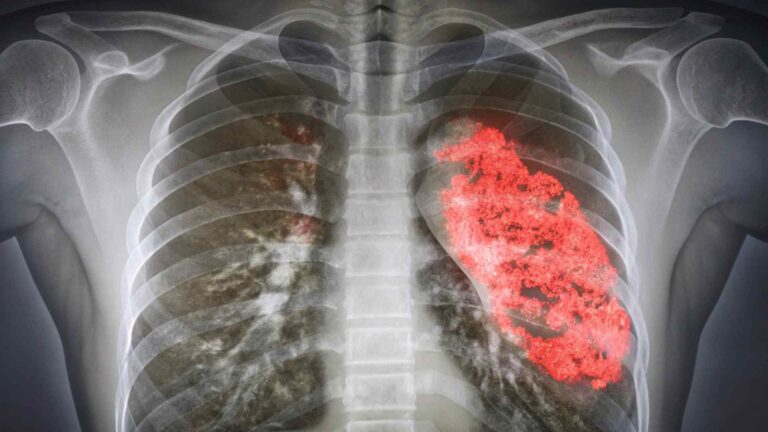

דלקת ריאות - Pneumonia

דלקת ריאות הוא מושג כללי לדלקת של אחת הריאות או שתיהן המתרחשת כאשר חיידקים, מפטריות או נגיפים בפה, אף או מערות האף מתפשטים לריאות. הזיהום גורם לשקיקי האוויר בריאות (נאדיות) להתמלא בנוזל או במוגלה.